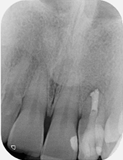

Pre-op X-ray

Pre-op

Pre-operative X-ray

Pre-operative